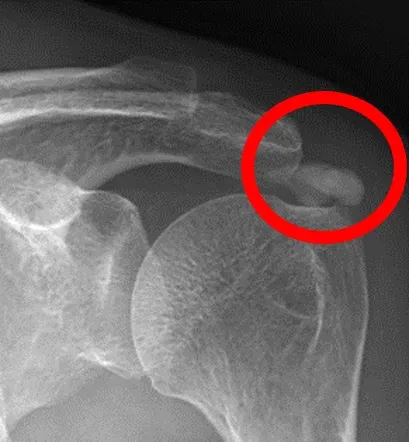

肩關節退化

肩關節置換

反置式人工肩關節

旋轉肌腱斷裂

旋轉肌群損傷

撞擊症候群

肩部肌腱撕裂

旋轉肌腱撕裂